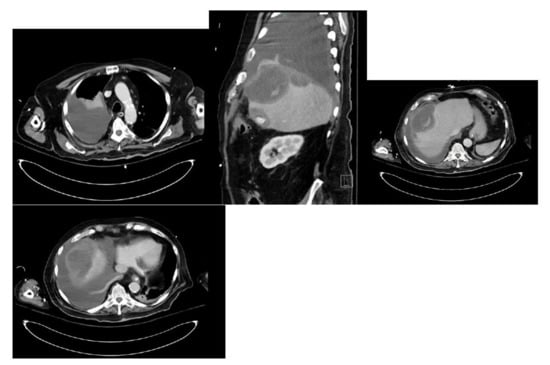

To better characterize the lesion, a CT abdomen was done. The CT showed a complex low-density right hepatic lobe subcapsular lesion measuring 13 × 8 × 7 cm, directly abutting the right anterior diaphragm, along with diffuse gross gallbladder wall thickening with cholelithiasis and a moderate right pleural effusion (Figure 3).

The patient underwent chest tube placement with the removal of 1600 cc of cloudy light-brown-colored fluid. Pleural fluid analysis was consistent with empyema, with WBC of 70,800 cells/mcL (61% neutrophils), glucose less than 10 mg/dL, LDH of 4821 IU/L, pH of 7.0, protein of 3.6 gm/dL, and Gram stain showing Gram-positive cocci in chains. Cytology was negative for malignant cells but showed severe acute inflammation and rare mesothelial cells. The blood culture on admission grew beta-hemolytic streptococci. The pleural fluid culture grew Streptococcus anginosus. On day two of hospitalization, the patient was scheduled for CT percutaneous drainage of liver abscess. However, the CT revealed a significant decrease in the size of the right subdiaphragmatic perihepatic collection to 1.5 cm in greatest thickness (Figure 4).

Figure 3. CT abdomen showing a complex low-density right hepatic lobe subcapsular lesion and a moderate right pleural effusion.